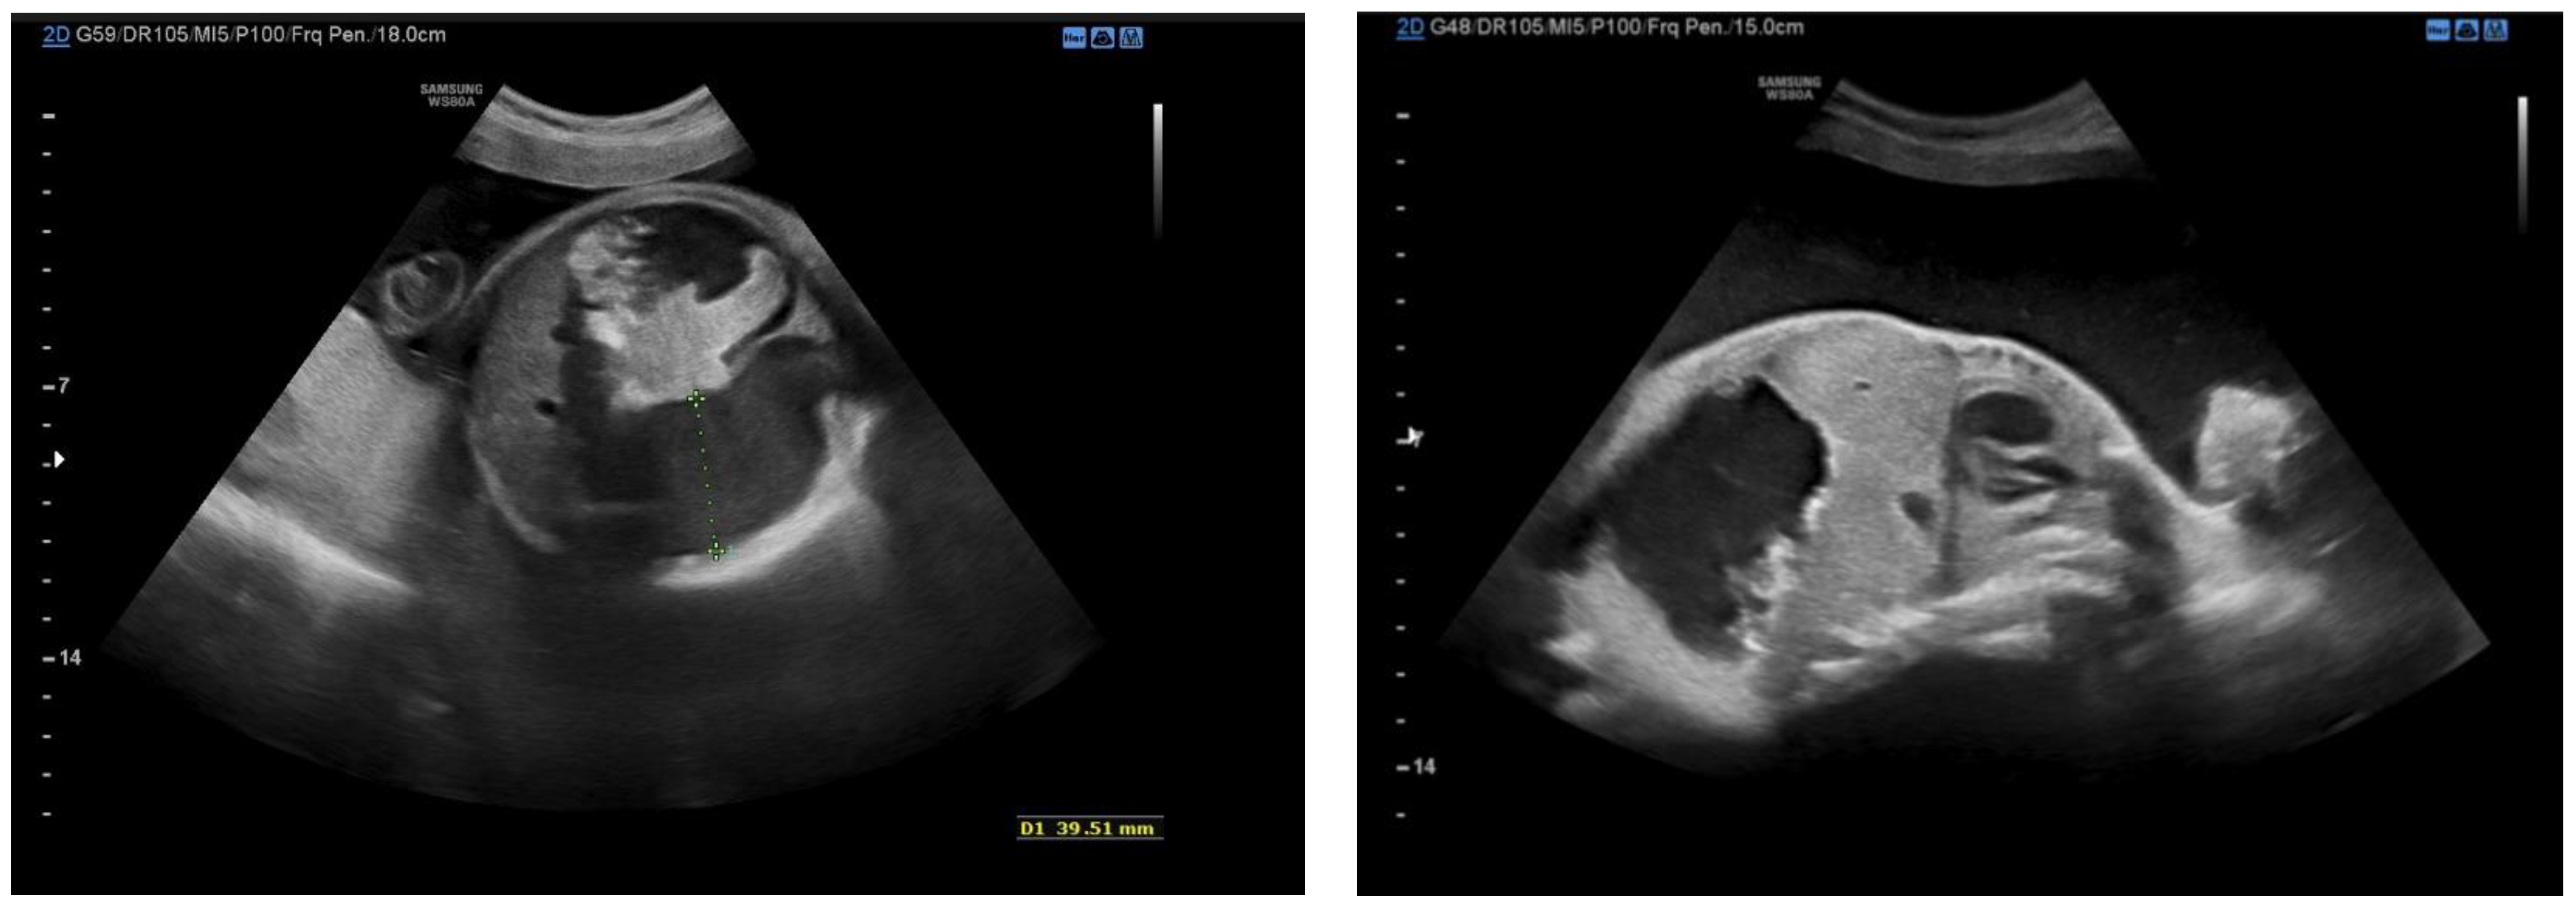

2.1. Case 1

2.2. Case 2